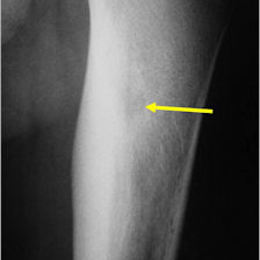

Radiographic imaging is used to help form a diagnosis. These include X-Ray, MRI, CT and Bone Scans

An example of an osteoid osteoma is shown.